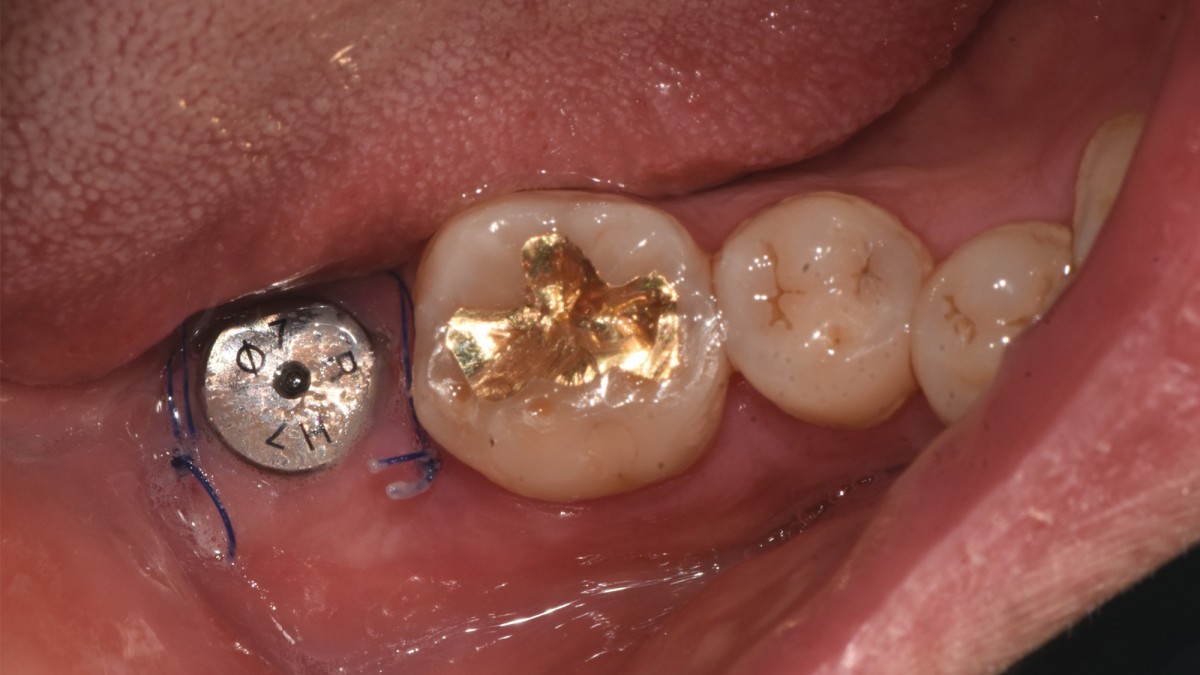

A 47-year-old male patient had a crown with an ill-fitting margin and crack-tooth syndrome in the lower 2nd molar. No systemic issue.

▲Arum Dentistry NB1 5*10